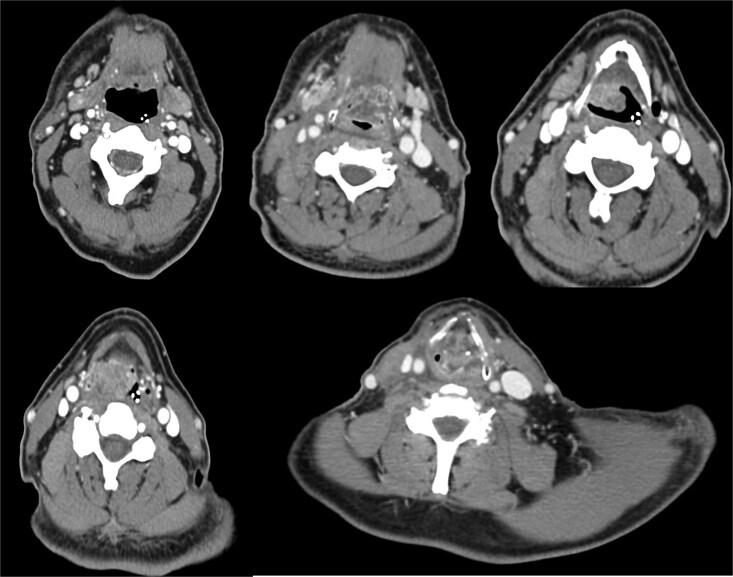

Neuroendocrine carcinomas (NECs) of the larynx are rare malignancies with aggressive behavior, histopathological diversity, and poor prognosis. Their management remains challenging due to limited case reports and the lack of standardized treatment guidelines. We conducted a comprehensive literature review to summarize classification, diagnosis, and treatment approaches for laryngeal NECs. Additionally, we present a representative case of a 64-year-old male patient diagnosed with large cell NEC of the larynx, treated with surgical resection and adjuvant radiotherapy, with long-term follow-up. Laryngeal NECs require a multidisciplinary approach, and treatment should be tailored based on tumor grade, stage, and histopathological subtype. Advances in molecular profiling and targeted therapies may improve patient outcomes in the future. Due to their rarity, further prospective studies and international collaborations are needed to establish evidence-based treatment guidelines.

喉神经内分泌癌(NECs)是一种罕见的恶性肿瘤,具有侵袭性、组织病理学多样性和预后不良的特点。由于病例报告有限且缺乏标准化治疗指南,其治疗仍然具有挑战性。我们进行了一项全面的文献综述,以总结喉NECs的分类、诊断和治疗方法。此外,我们还介绍了一例64岁男性患者的典型病例,该患者被诊断为喉大细胞NEC,接受了手术切除和辅助放疗,并进行了长期随访。喉NECs需要多学科方法,治疗应根据肿瘤分级、分期和组织病理学亚型进行个体化定制。分子谱分析和靶向治疗的进展可能会在未来改善患者的治疗效果。由于其罕见性,需要进一步的前瞻性研究和国际合作来建立基于证据的治疗指南。